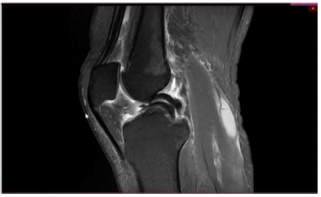

Um paciente de 19 anos de idade sofreu entorse do joelho

direito durante agachamento em partida de futebol. Foi

retirado do campo e queixando-se de dor na face interna do

joelho. Foi levado ao hospital mais próximo e, ao ser

examinado, percebeu que não conseguia estender

completamente o joelho. Não conseguia flexionar totalmente

o joelho também. Notaram-se ainda, edema e o sinal da tecla.

Considere que, no caso clínico descrito, foi realizado o exame complementar, conforme apresentado. Essa figura mostra